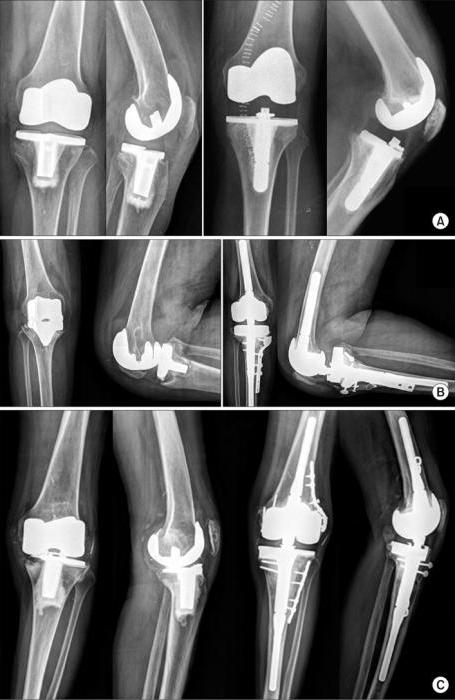

Prices, of course, are horrifying, but there is one aspect that scares many even more: the life of the prosthesis. Modern systems are not eternal help. Over the years, they gradually collapse. The term of operation is determined by several parameters. One of the most important is the method of attaching an artificial system to bone tissue. In some cases, the components of the prosthesis are literally hammered into the bone, and gradually the objects grow together. In medicine, this is called osseointegration. The joint elements when applying this technique are firmly fixed, so the system will last quite a long time.

The specified technique is far from always implemented. Often the quality of the bone simply does not allow such a prosthetics, but the reasons may be of a different kind. An alternative is the use of bone cement, that is, such a solidifying mass that allows you to quickly fix the prosthesis.

Friction pair

This parameter of the prosthesis directly determines the duration of its service life and the effect on the patient’s organic tissues. In fact, a joint is a joint whose components rub against each other. If in technology the process is smoothed by the presence of lubricant, then in the human body there is none, therefore, the components wear out over time. The degree of wear is directly related to the survival of the joint. It is determined by the materials used and the number of movements made by a person.

In order for the joint to live longer, it is necessary to install systems with the most effective friction parameters, as well as reduce the number of motion cycles. The longest wear periods are characteristic of systems in which ceramics are involved, but the price of such prostheses is also the highest.